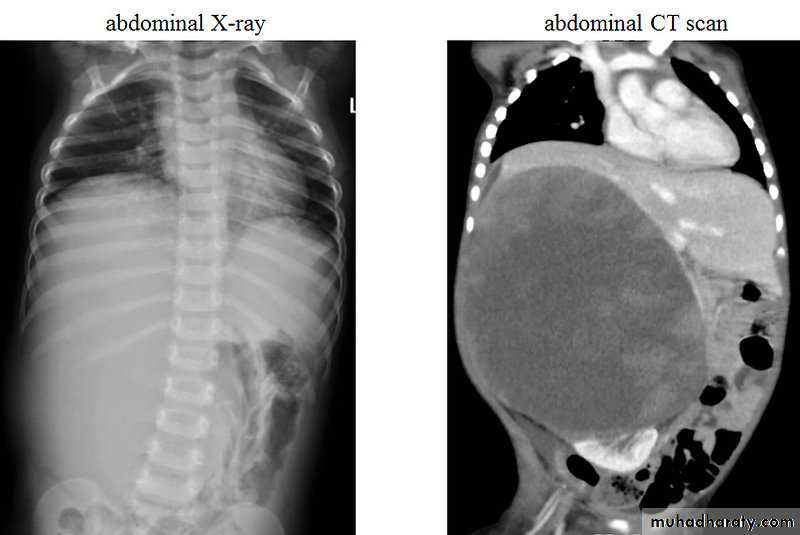

Wilms Tumor ;Nephroblastomma

Most common malignant abdominal neoplasm in children.Peak age: 2-3 years.

It arise from kidney, 90 % unilateral, 10 % bilateral.

Clinical presentation: Palpable abdominal mass, hypertension or hematuria.

Radiological features:

Appear as soft tissue opacity on plain x ray displacing the bowel loops.

On CT scan appear as a large heterogeneous well defined solid mass.

Sometimes there is a calcification and cystic formation.It cause displacement of adjacent structures and may cross the midline.

Treatment: surgery and radiotherapy.

Prognosis: cure rate about 90 %